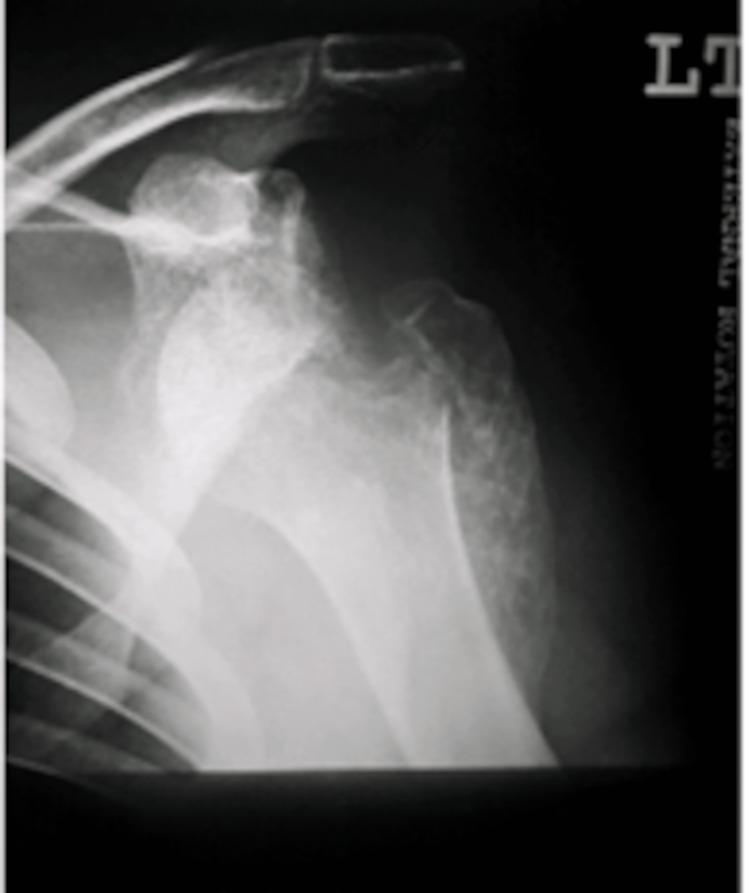

Bilateral shoulder dislocations are a rare occurrence and can be categorized as either symmetric (both humeral heads dislocate in the same direction) or asymmetric (wherein the humeral heads dislocate in different directions). Shoulder dislocations may be overlooked if they are the result of systemic injury; if diagnosed >21 days after occurring, they are considered chronic dislocations. We describe the case of a 31-year-old male who presented with an eight-week history of bilateral shoulder pain. His onset of pain coincided with a seizure secondary to Chikungunya encephalitis. Clinical and radiological examination demonstrated bilateral symmetric anterior shoulder dislocation with associated greater tuberosity fractures and extensive callus formation bilaterally. Open surgical management was performed first on the left shoulder via the deltopectoral approach. The callus was removed, the greater tuberosity fragment lifted off, reattached to the original position, and held in place with sutures and proximal humeral locking plates. The right shoulder was reduced six weeks after the left shoulder due to patient preference; the reduction utilized the same approach as with the left shoulder. Post-operatively the patient was immobilized, and physiotherapy commenced. He achieved a satisfactory range of motion four months post-operation. Physicians should be cognizant that shoulder pain after a convulsive seizure may signify shoulder dislocation. Thorough clinical and radiological examinations are warranted in such an instance. There exists no consensus on the treatment of chronic shoulder dislocations, but it is recommended that closed reduction only be attempted up to six weeks post-dislocation due to the high risk of iatrogenic fractures and neurovascular damage beyond this time.

双侧肩关节脱位较为罕见,可分为对称型(两个肱骨头向同一方向脱位)或不对称型(肱骨头向不同方向脱位)。如果双侧肩关节脱位是由全身损伤导致的,可能会被忽视;如果在脱位发生21天以后才被诊断出来,则被视为慢性脱位。我们报告一例31岁男性患者,其双侧肩部疼痛长达8周。他的疼痛发作与基孔肯雅热病毒性脑炎继发的癫痫发作同时出现。临床和影像学检查显示双侧肩关节对称前脱位,伴有大结节骨折及双侧广泛骨痂形成。首先通过胸大肌三角肌入路对左肩进行切开手术治疗。清除骨痂,将大结节骨块掀起,重新复位并固定到原始位置,用缝线和肱骨近端锁定钢板固定。由于患者的选择,右肩在左肩手术后6周进行复位;复位采用与左肩相同的方法。术后患者进行制动,并开始物理治疗。术后4个月,患者的活动范围恢复到令人满意的程度。医生应认识到惊厥性癫痫发作后的肩部疼痛可能意味着肩关节脱位。在这种情况下,有必要进行全面的临床和影像学检查。对于慢性肩关节脱位的治疗目前尚无共识,但由于脱位超过6周后进行手法复位会有较高的医源性骨折和神经血管损伤风险,因此建议仅在脱位后6周内尝试进行闭合复位。